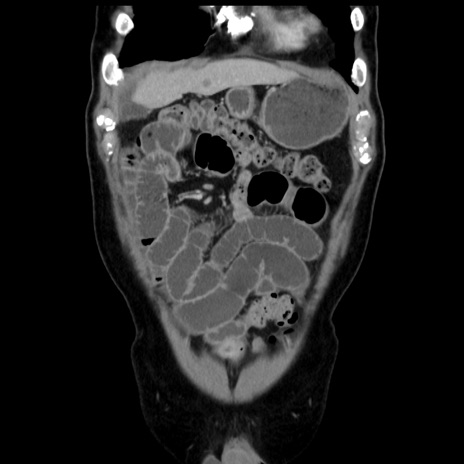

症例16(冠状断像)

【症例】 70歳代男性

【主訴】 腹痛、嘔吐

【現病歴】 約1ヶ月前より間欠的に腹痛と嘔吐あり、当院消化器内科を受診したところCTで多発する肝臓のLDAを指摘され、精査中であった。以降は消化器症状は安定していたが、2日前より嘔気と腹痛があり、同日より排便・排ガスが消失した。改善認めず、 本日、救急外来を受診した。